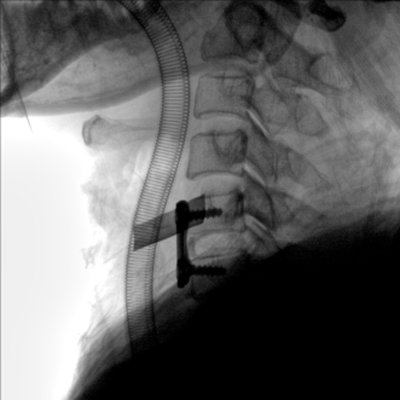

大尺寸動態(tài)平板探測器,高DQE、低噪聲、圖像清晰。采用多分辨率圖像增強處理技術(shù),不同部位不同圖像處理算法,滿足客戶多樣化的需求。

采用智能變頻脈沖透視技術(shù),優(yōu)化圖像質(zhì)量的同時降低輻射劑量,呵護(hù)醫(yī)患健康